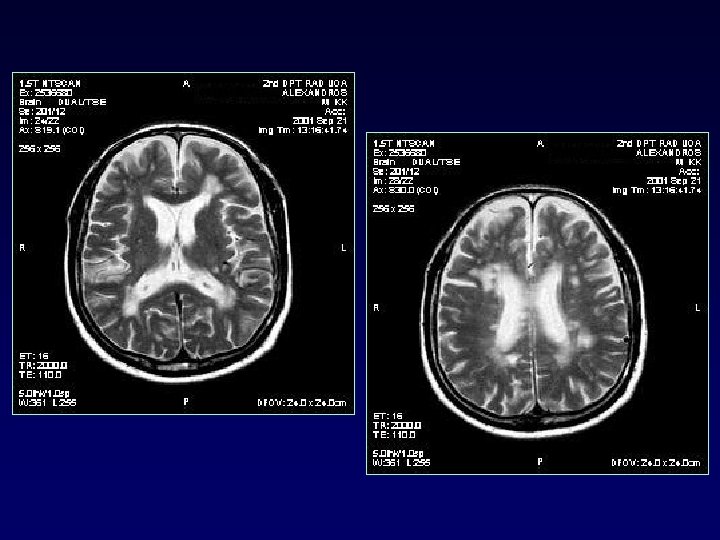

PERIVENTRICULAR - JUXTACORTICAL

JUXTACORTICAL

INFRATENTORIAL